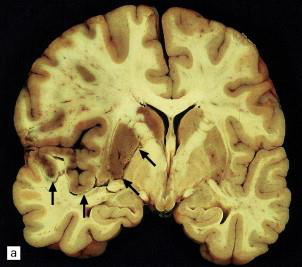

Subfalcine Herniation